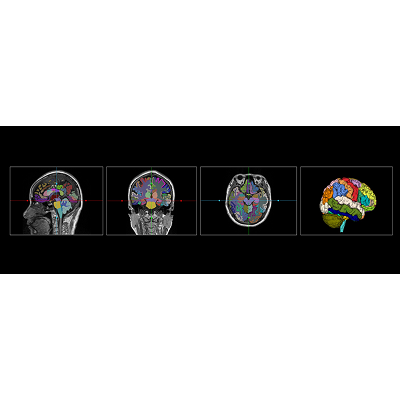

联影智能MR脑结构智能分析系统可快速精准地实现大脑111个脑区分割,自动计算脑区体积、不对称性指数、MTA评分等多维分析指标,有效提高阅片效率,为医生诊断提供临床辅助信息。该系统可早期预警由多种疾病引起的脑组织体积变化,随访跟踪病情发展,有助于神经退行性疾病等的早期筛查与干预。同时AI检测结果可通过图文报告和表格形式导出,辅助医生临床工作和后续科研分析。

联影智能脑结构人工智能分析系统通过精准分割大脑111个脑区,并自动计算多维分析指标,为医生提供神经退行性疾病等疾病的早期诊断和精准治疗依据。该系统支持多角度参数分析和多应用场景的图文报告生成,不仅提高了医生的工作效率,还优化了患者的就医体验,对提升医疗服务质量和推动脑科学研究具有重要意义。